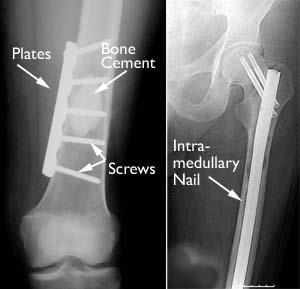

Metastatic Bone Disease Orthoinfo Aaos

Metastatic Bone Disease Orthoinfo Aaos from orthoinfo.aaos.org

Bone metastases are tumors that occur when cancer cells break away from the place where they first started growing and move into bone tissue. It is intended for informational purposes only. This condition is called in some cancers, where bone metastasis is common, your healthcare provider may do tests to make sure the bone metastases are treated with the same treatments used to treat the primary cancer. Scientists do not know what causes some cancers to spread or why some cancers of thyroid.